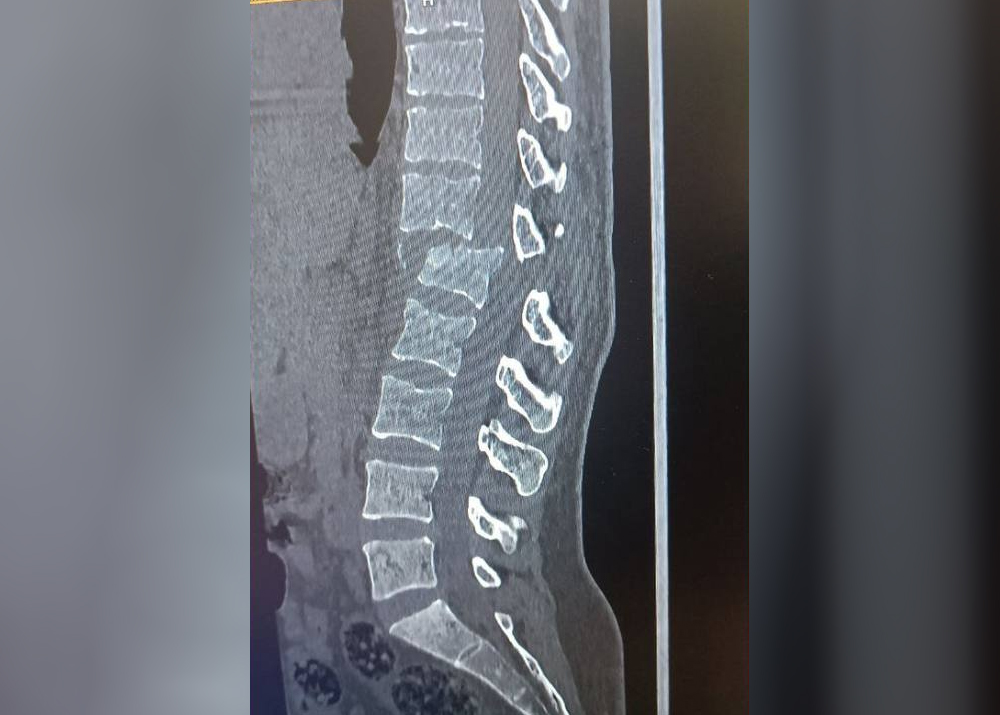

Утром 14 августа на своем "Дамасе" он сбил супругу, когда она шла по обочине дороги. Женщина получила тяжелые травмы: перелом позвоночника, повреждение нервных окончаний и паралич нижней части тела. Сейчас она находится в больнице, ей требуется дорогостоящая операция в Ташкенте, на которую у родственников нет денег. Муж, виновный в ее инвалидности, отказывается помогать с лечением.